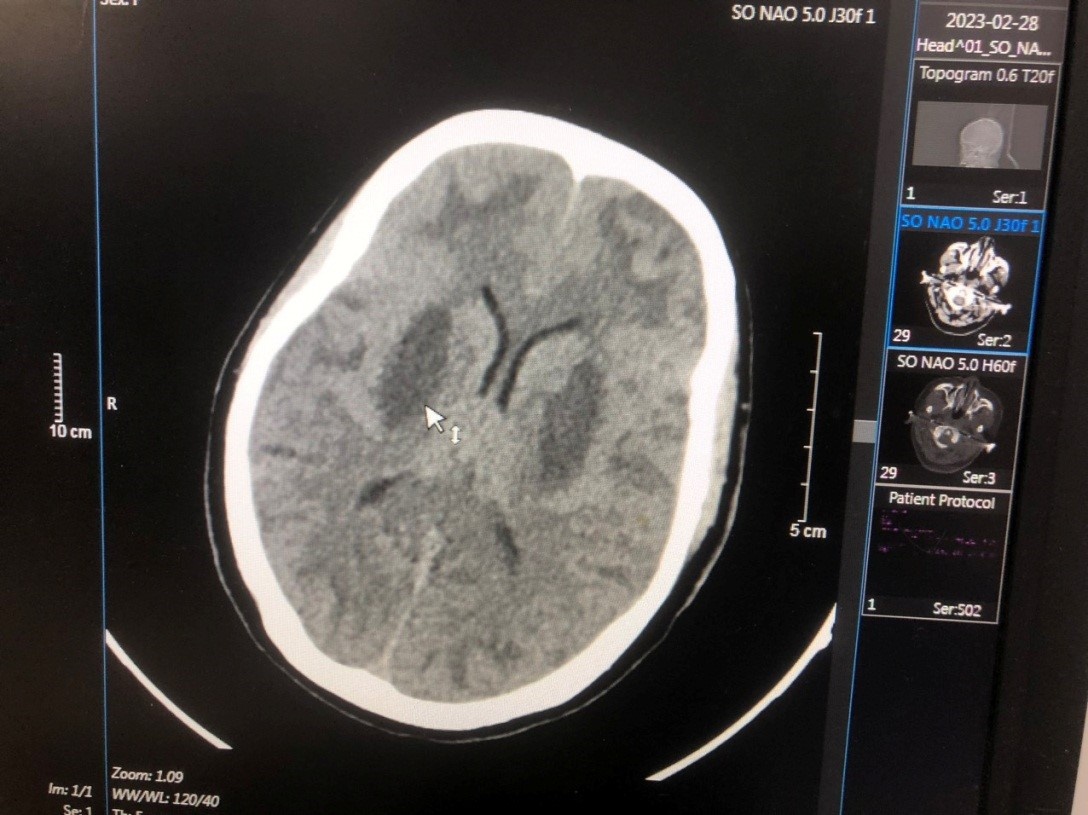

Vu nhiem doc methanol anh 1

Hình ảnh tổn thương não của bệnh nhân T.V.N.. Ảnh: BVCC.

Sau đó, bệnh nhân được chuyển tới Bệnh viện Bạch Mai trong tình trạng hôn mê, tụt huyết áp, nhiễm toan chuyển hóa nặng, tổn thương não nặng hai bên, nồng độ methanol trong máu là 125 mg/dL, không có ethanol. Bệnh nhân đã được cấp cứu điều trị hồi sức giải độc lọc máu, hiện tri giác có cải thiện nhưng não vẫn tổn thương và phù não nhiều, tổn thương mắt.